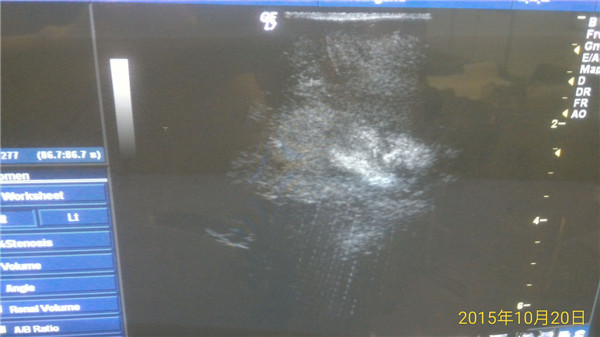

术中超声